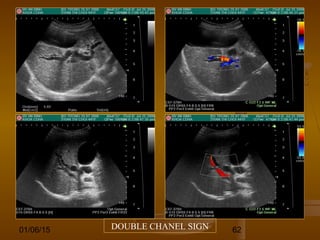

DẤU HIỆU SÚNG SĂN HOẶC KÊNH ĐÔIDẤU HIỆU SÚNG SĂN HOẶC KÊNH ĐÔI

(DOUBLE CHANNEL SIGN - SHOTGUN SIGN)(DOUBLE CHANNEL SIGN - SHOTGUN SIGN)

 Hai cấu trúc ống chạy song song trong gan do TMCHai cấu trúc ống chạy song song trong gan do TMC

và đường mật trong gan bị dãn tạo thành.và đường mật trong gan bị dãn tạo thành.

 Âm tính giảÂm tính giả: trong tắc mật cấp tính.: trong tắc mật cấp tính.

 Dương tính giảDương tính giả: dãn ĐM gan trong xơ gan, bệnh: dãn ĐM gan trong xơ gan, bệnh

nhân sau cắt túi mật (OMC và đường mật trong gannhân sau cắt túi mật (OMC và đường mật trong gan

dãn).dãn).

01/06/15 62DOUBLE CHANEL SIGN